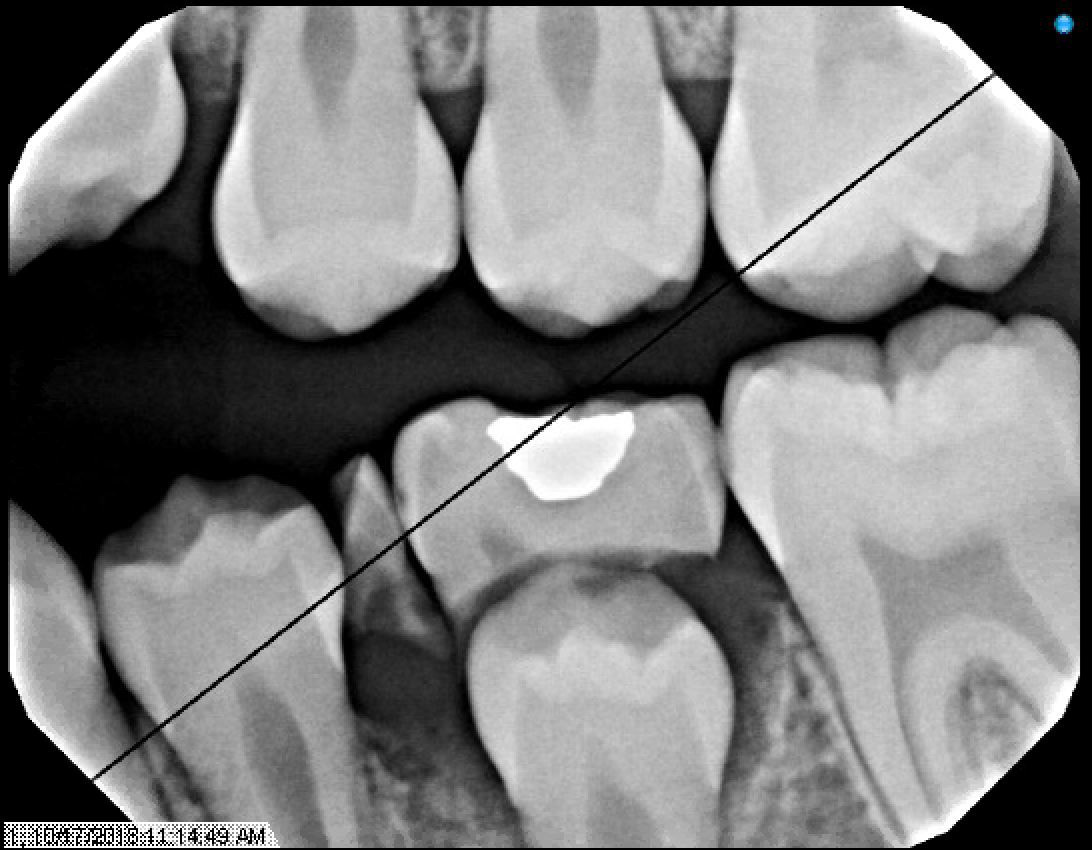

Figures 9 & 10: Preoperative bitewings of Right and Left

Figure 11: Preoperative Panoramic image

Radiographs from 10/17/18 - School Based Dental Program @ PS188

Since this patient was already seen a year ago in NYUCD. This visit was considered a recall visit.

Due to the clinical carious lesions present - 2 BW radiographs were recommended to observe any interproximal carious lesions (also to update the treatment plan that was never fulfilled) and PA#8 to observe the location of mesiodens and any update in eruption of #8 or the mesiodens.

Radiographic Interpretation revealed: Carious lesions in #3-O, #A-O, #14-O, #19-OB, #K-MOD, root tip present in tooth #L, #30-O, Mesiodens present ( disrupting the proper eruption of tooth #8) ***

Figures 12, 13, & 14: Recall bitewing radiographs 10/17/18 @PS188 School Based Dental Program